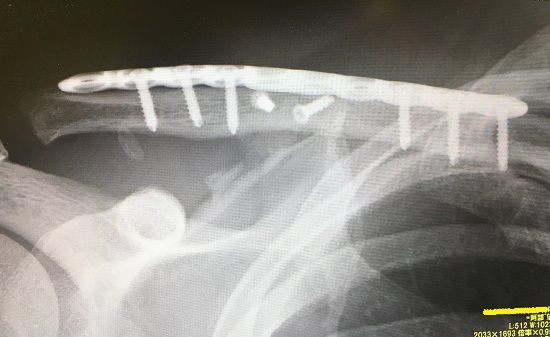

さて、今月の僕の鎖骨くんの経過です↓

鎖骨の粉砕箇所が、かなり白っぽくなってきたような。

リハビリ頑張ります-☆